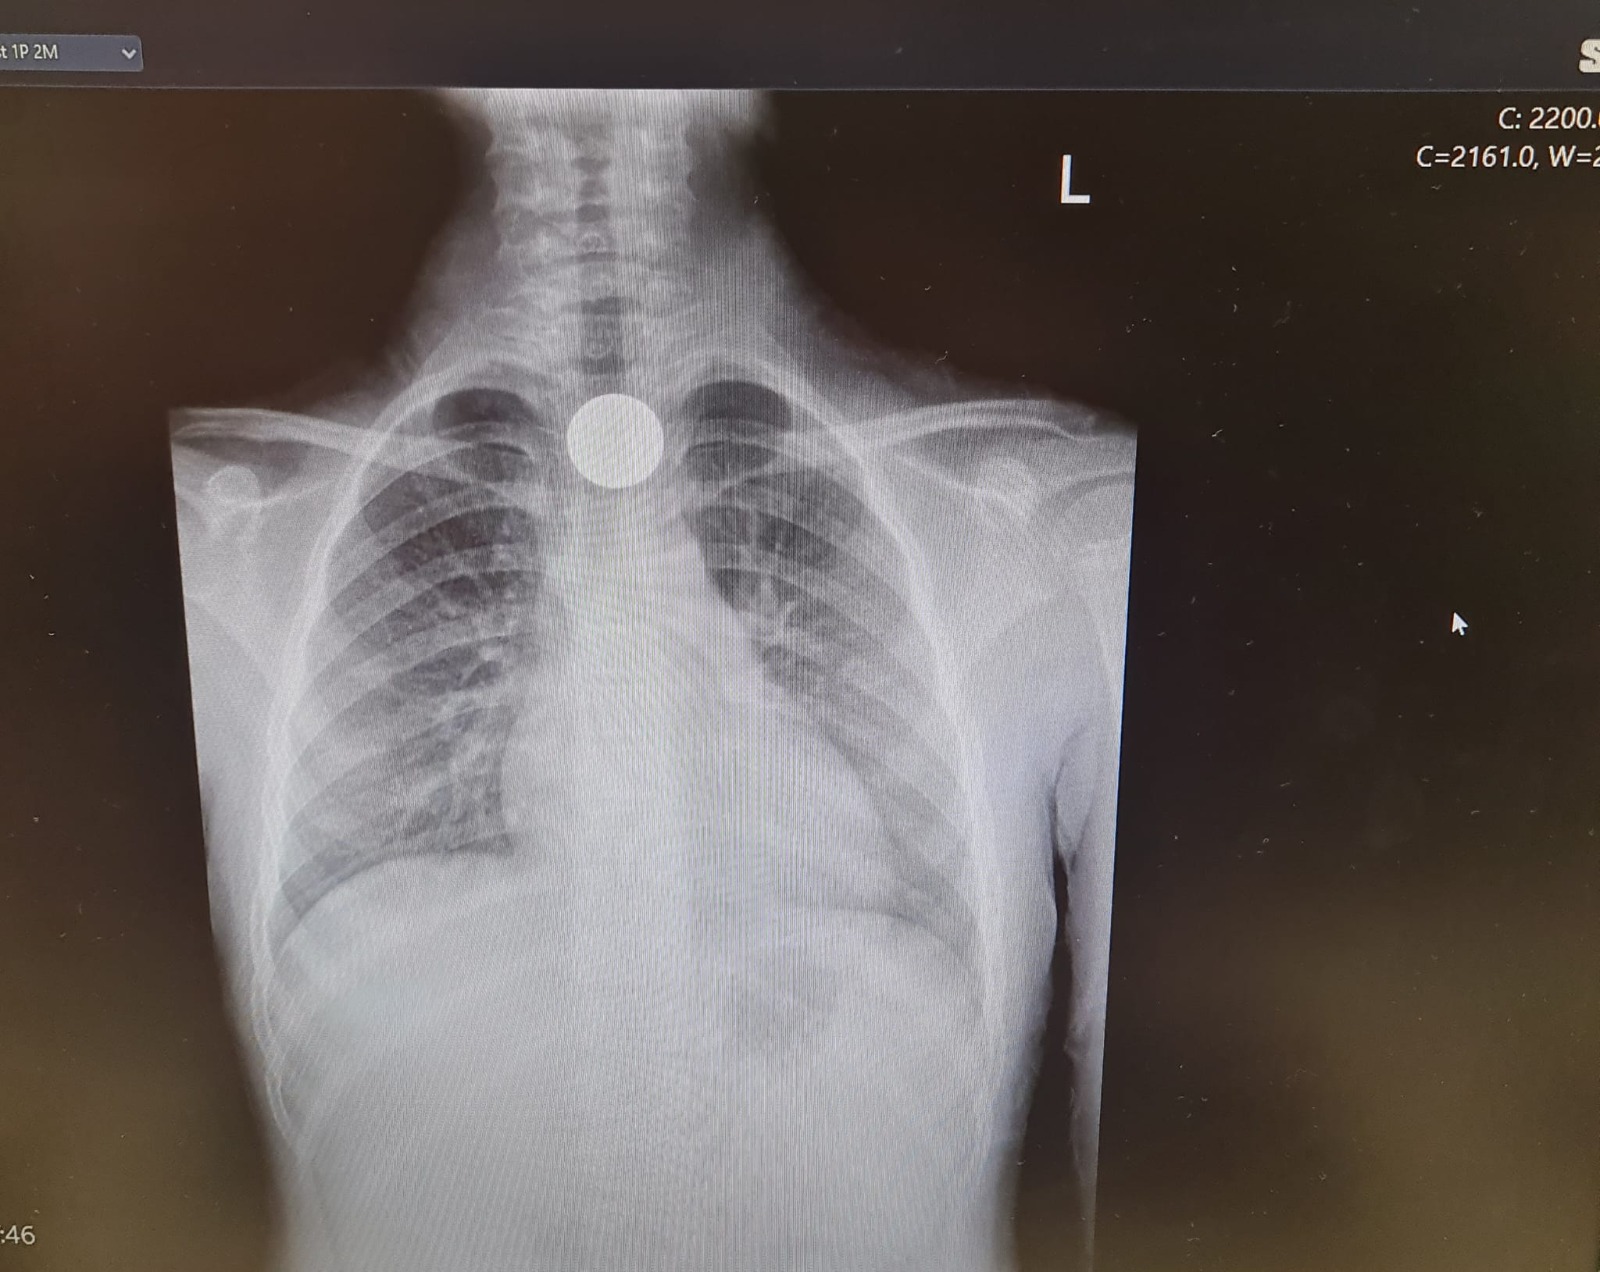

הילדה בלעה מטבע, הרופאים הצילו את חייה

האם המבוהלת לקחה את בתה אל המרכז הרפואי ברזילי ושם הצליחו הרופאים להוציא את המטבע מהוושט.

כהן הללי, ילדה בת 6 וחצי מאשקלון, בלעה אתמול מטבע של 10 אגורות בבית הספר. הללי הגיעה למיון, נשלחה לצילום, שבו נצפה מטבע בוושט. המטבע הוצא בפעולת גסטרוסקופיה. הללי התאוששה ושוחררה לביתה במצב טוב.

צילום: דוברת המרכז הרפואי ברזילי